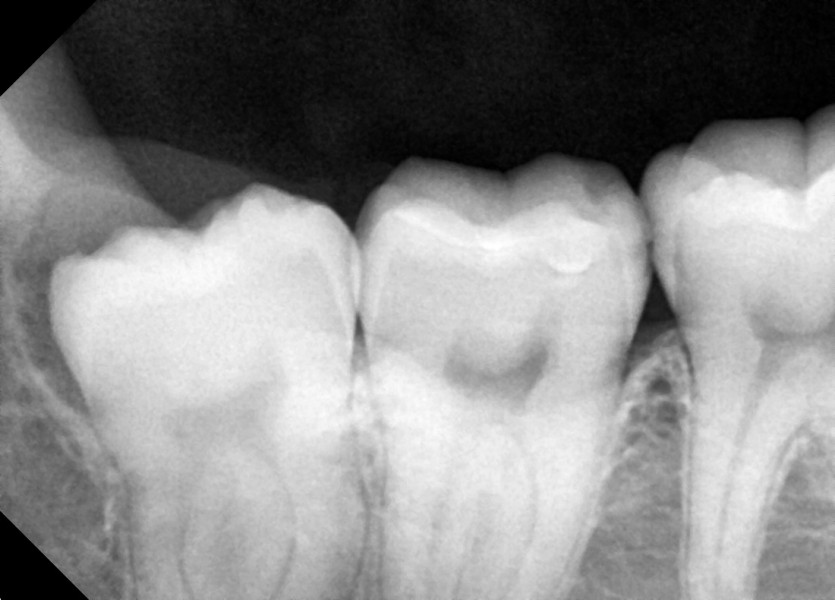

#18,48 사랑니 발치

구강 외과 전문의가 당일 발치했습니다.